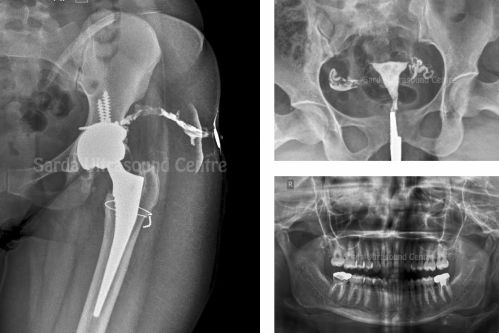

Digital X-Ray and OPG

We offer digital X-ray services for various diagnostic needs, as well as OPG for dental imaging. All X-ray procedure facilities like HSG, RGU, IVP, Sinogram, barium studies, etc are available at SUC.